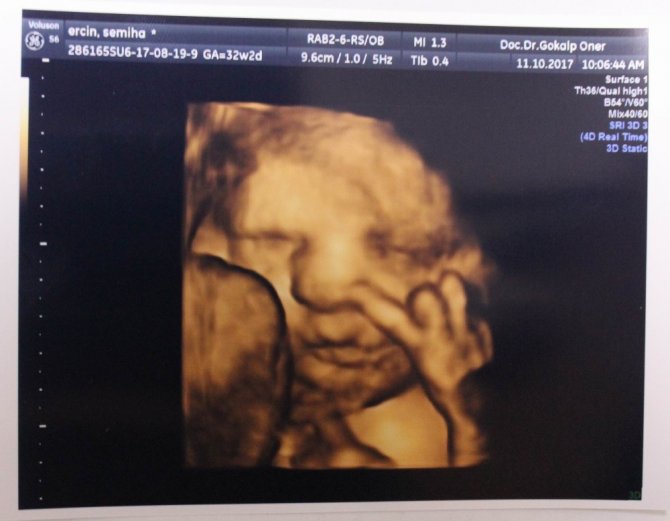

Anne karnındaki bebeklerin çekildiği dört boyutlu ultrason fotoğraflara takılan pozlar bazen şaşırtıyor. Henüz 22 haftalıkken zafer işareti yapan bebeğin fotoğrafı bunlardan en ilgi çekici olanı.

Memorial Kayseri Hastanesi Kadın Hastalıkları ve Doğum Uzmanı Doç. Dr. Gökalp Öner'in yaklaşık 2 yıldır çektiği 400'ün üzerinde, dört boyutlu ultrason fotoğraflara takılan anne karnındaki bebeklerin ilginç pozları dikkat çekiyor. Zafer işareti yapan, burnunu karıştıran, dilini çıkaran, uzun hava çeken, düşünen bebek fotoğrafları ebeveynleri hem mutlu ediyor hem de şaşkınlığa uğratıyor.

Mutlu geçirilmesi gereken hamilelik dönemini bu fotoğraflarla renklendirdiklerini dile getiren Doç. Dr. Gökalp Öner, "Bu fotoğraflarda bazen ilginç pozlar yakalıyoruz. Bebeklerimiz ağlarken, gülerken, düşünürken, zafer işareti yaparken, burnunu karıştırırken... Bunları yakaladığımızda ailenin de bizim de hoşumuza gidiyor. Böyle mutlu anları paylaşıyoruz. Çünkü gebelik süreci ve doğum, düğün gibi mutlu geçirilmesi gereken bir süreç" ifadelerini kullandı.